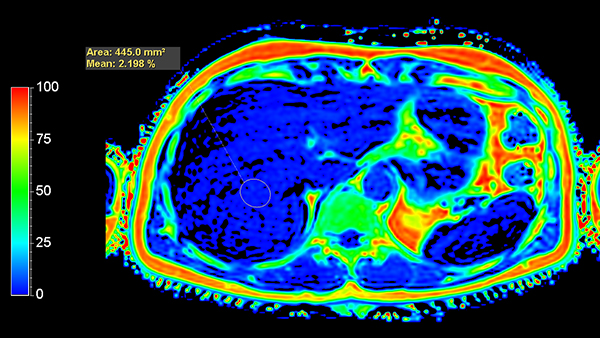

Axial mDIXON Quant (Fat Fraction)